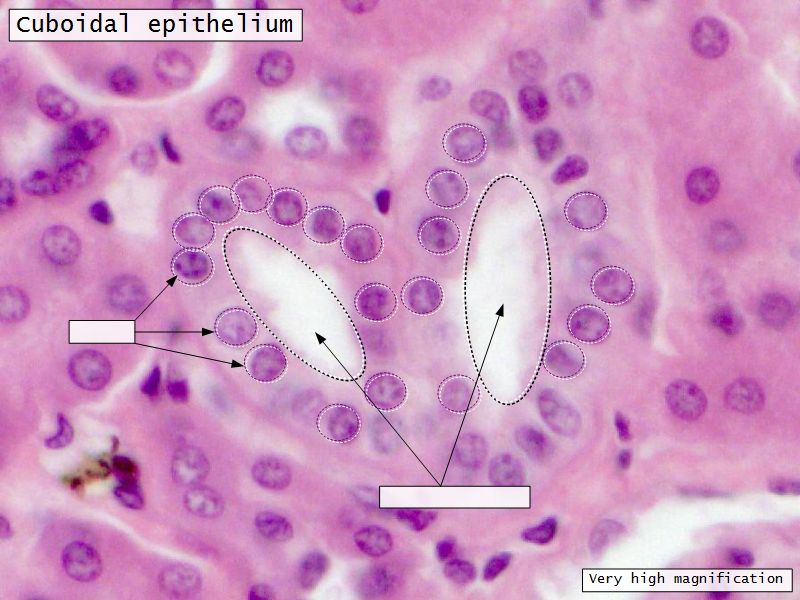

Loop of Henle - thin

- Narrow lumen

- Thin wall

- Squamous epithelium

- Looks like capillaries

Loop of Henle - thick

Continuation of descending and ascending tubuliDistal convoluted tubuli

- Joins collecting tubule

- Cuboidal epithelium

- Light stained

- Wide looking lumen

- Indistinct borders